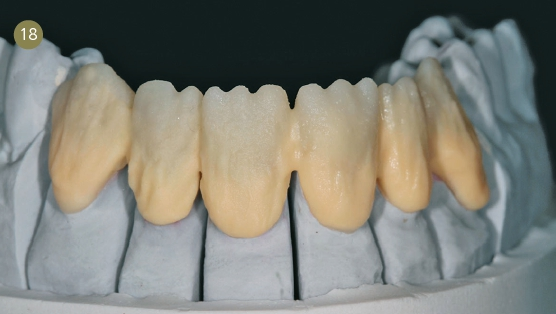

Wax-up

Es half der Patientin sehr, das Wax-up auf dem Gipsmodell anzuschauen. Gute Erfahrungen, in bestimmten Fällen ein Waxup zu fertigen und es mit dem Behandler zusammen mit den Patienten zu besprechen, machen wir immer wieder. Gerade bei Patienten mit einer hohen Erwartung ist es essenziell, sie in die Behandlungsplanung mit einzubeziehen und laienverständlich vorzugehen. So haben wir auch der Patientin genau dargelegt, wie wir zu ihrer neuen Zahnform kamen. Mithilfe des „Digital Smile Design“ nach Dr. Christian Coachman zeigten wir ihr unsere Vorstellung der bestmöglichen Versorgung. Dies ist für mich unerlässlich in der täglichen Arbeit geworden. Auch die Patienten lieben diese Art der Kommunikation zusätzlich zum Wax-up auf dem Gipsmodell.